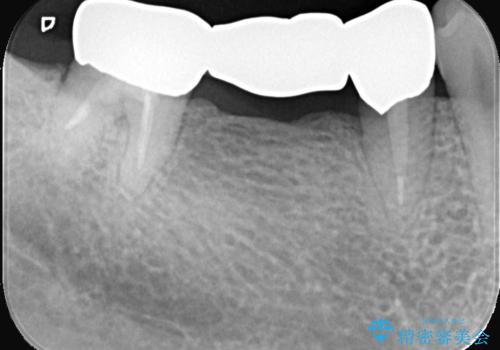

セラミックに比べ、破折リスクの少ない金属を使用したブリッジでのやり替えとなりました。

両支台歯が失活歯のため、どちらかもしくは両方の歯が破折した際、再度ブリッジを除去した治療が必要になるリスクとインプラント治療のご提案もさせていただきましたが、ブリッジでの治療を希望されました。

右下5番は支台歯CR築造を行っています。